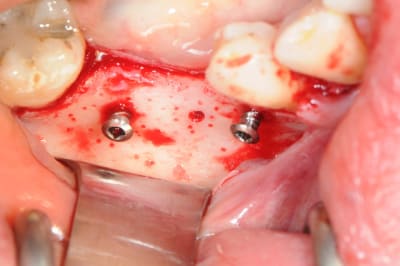

CAS 1

demande de restauration avec implant, mais, ne veut pas entendre parler de greffes et greffons.

la ROG lui semble plus "naturel".

4 après ouverture

7-8: et voilà 3 vis qui vont maintenir ma membrane au dessus de l'os.

9-10-11: la membrane maintenue par deux pins sur la table interne osseuse, comblement osseux recouvrant les têtes des vis puis je rabat la membrane que je fixe sur la table osseuse externe